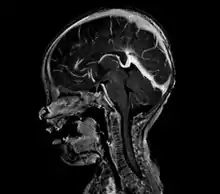

| Large arteriovenous malformation of the parietal lobe | |

A cerebral AVM diagnosis is established by neuroimaging studies after a complete neurological and physical examination.[5][12] Three main techniques are used to visualize the brain and search for an AVM: computed tomography (CT), magnetic resonance imaging (MRI), and cerebral angiography.[12] A CT scan of the head is usually performed first when the subject is symptomatic. It can suggest the approximate site of the bleed.[3] MRI is more sensitive than CT in the diagnosis, and provides better information about the exact location of the malformation.[12] More detailed pictures of the tangle of blood vessels that compose an AVM can be obtained by using radioactive agents injected into the blood stream. If a CT is used in conjunction with an angiogram, this is called a computerized tomography angiogram; while, if MRI is used it is called magnetic resonance angiogram.[3][12] The best images of a cerebral AVM are obtained through cerebral angiography. This procedure involves using a catheter, threaded through an artery up to the head, to deliver a contrast agent into the AVM. As the contrast agent flows through the AVM structure, a sequence of X-ray images are obtained.[12]